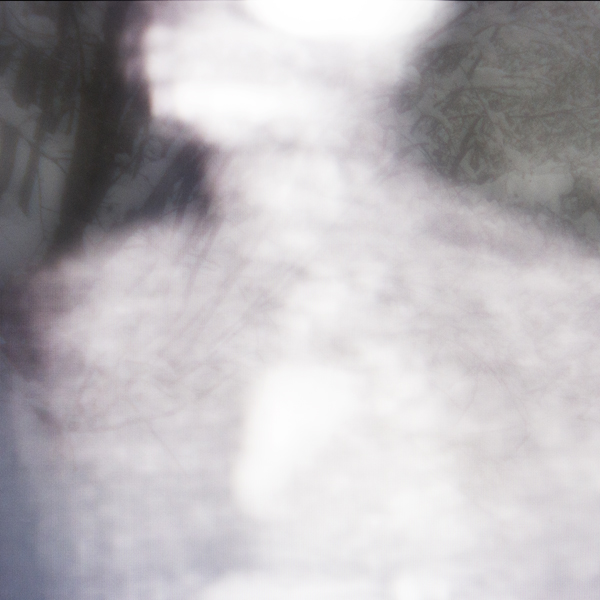

The physical or emotional turmoil that is inferred by the medical transparency of the human image is tempered by recognizable landscape. The natural world represents a place of peace and sanctuary.

These photographs illustrate how art and technology are intricately connected. While opposites in so many ways, they must co-exist. Without the landscape imagery, we are left with medical images, cold and impersonal. However, it’s the scientific and technological aspects that help breathe life into our human environment, leaving us with a true reflection of the human spirit, including a reminder of our shared strengths and vulnerabilities.